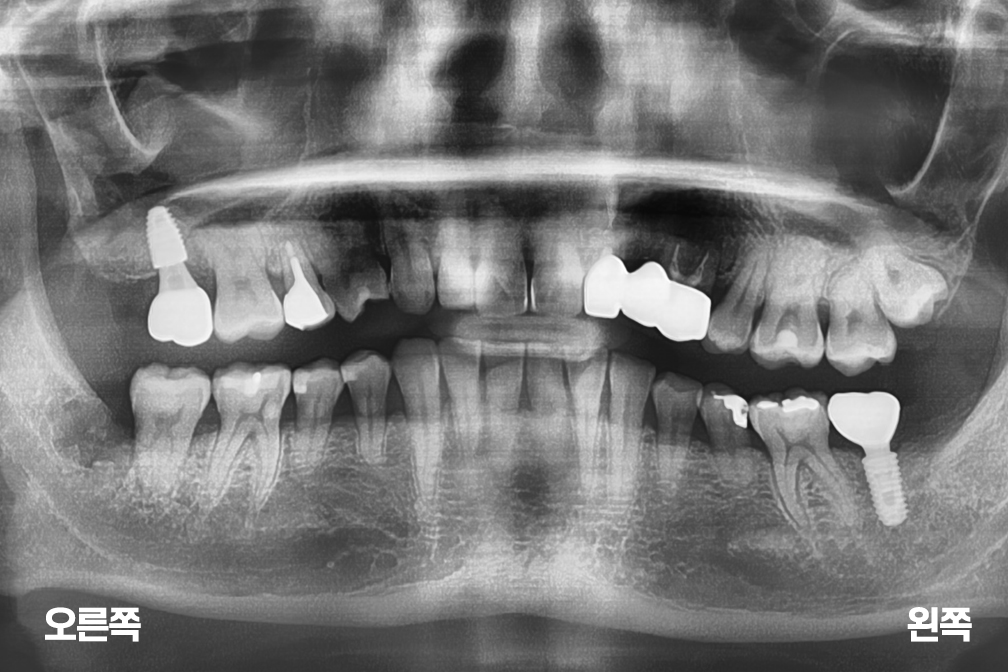

임플란트 오른쪽 윗 어금니 임플란트 및 왼쪽 아래 어금니 보철

Before 2020년 7월 11일